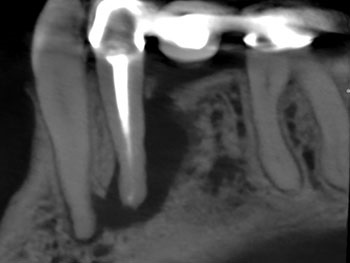

Fig. 1: Preoperative PA.

Case 2: A U-shaped lesion

Tooth #30 presented with a diagnosis of previously treated and symptomatic apical periodontitis. The radiographic lesion encompassed both sides of the mesial root, forming a U-shaped lesion. Periodontal probing extended to the apex. The prior endodontic root preparations were relatively large, compared with the root canals on the patient’s other untreated teeth. Because the bone loss associated with a U-shaped lesion encompasses both sides of a root, it might be considered even more indicative of a potential VRF than a J-shaped lesion.

This patient had been examined by an endodontist, who recommended extraction because of a VRF. Although multiple risk factors were identified, no fracture was seen upon access, and this tooth was successfully retained through nonsurgical retreatment.

Fig. 5: Preop PA.